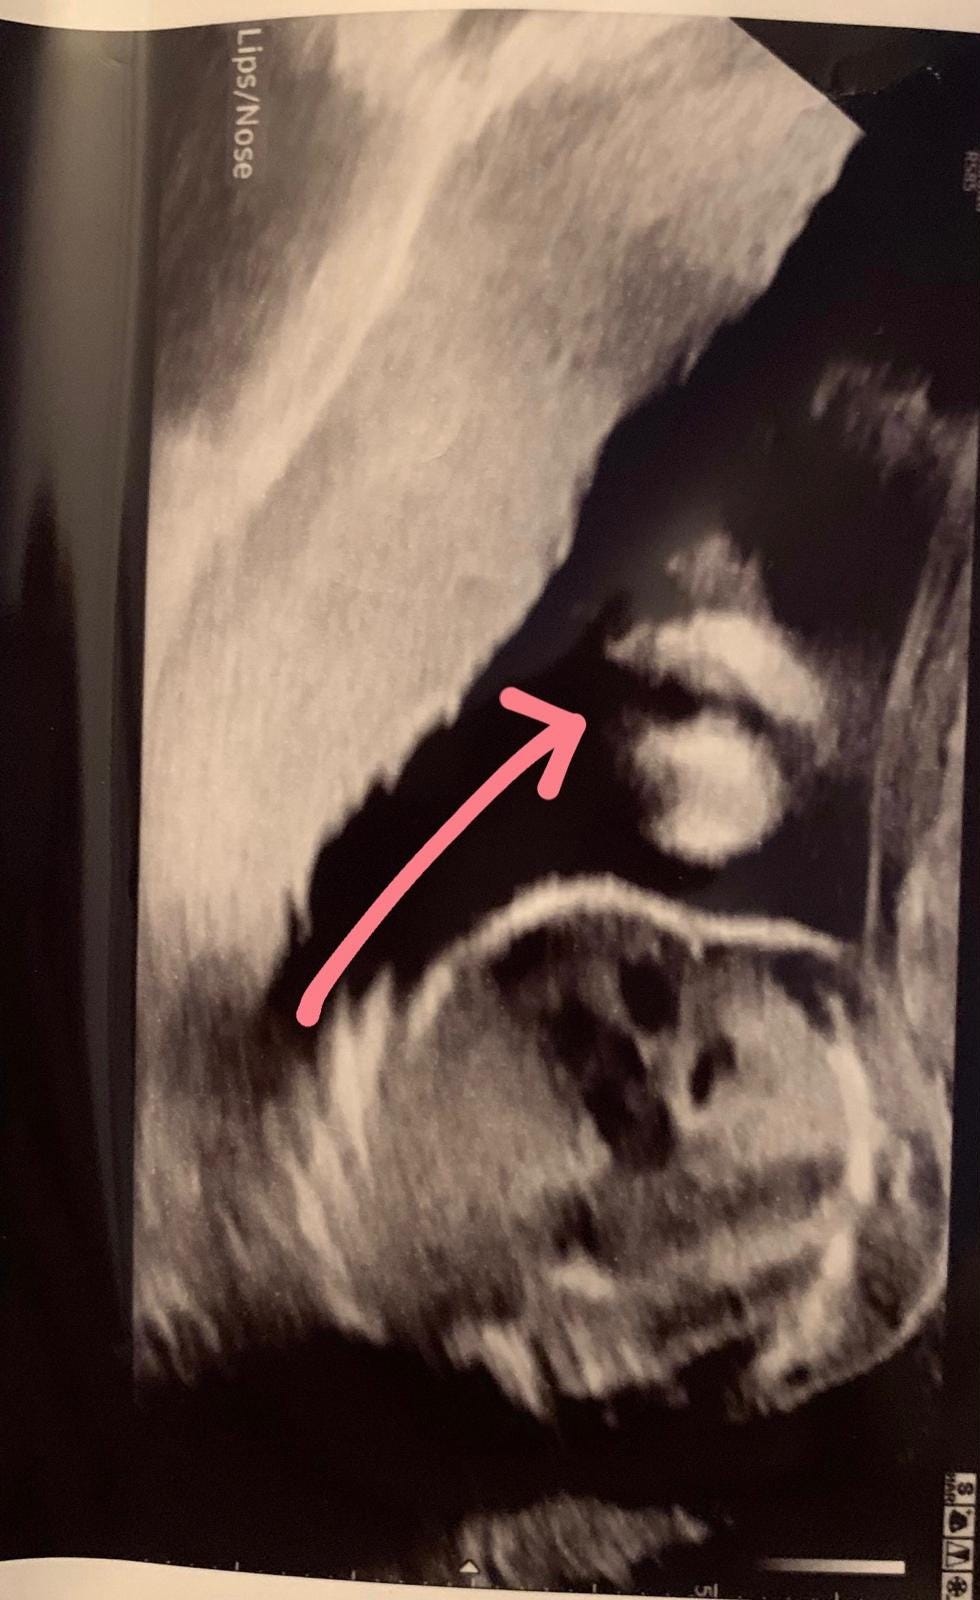

How could you get through a pregnancy without scans now they existed? Not just for the practical reassurance - knowing your baby is growing properly, that everything is developing as it should, that you were both okay - but for the joy of it. The chance to see them on those grainy black and white images that you’d stare at for hours, trying to make out a profile, a hand, a foot - some proof that there was actually a whole person in there - that you hadn’t dreamed the whole thing up.

Flash forward 5 years and I vividly remember seeing my sons lips in a scan picture, all smooshed. It’s one of my favourites. I’d marvel at it over and over and over again - before I knew his face like it was my own. When he was finally in my arms that scan picture came out again, so I could compare. There they were. Those perfect, now milk soaked, lips. Lips that I’d grown from scratch. What a wonder.